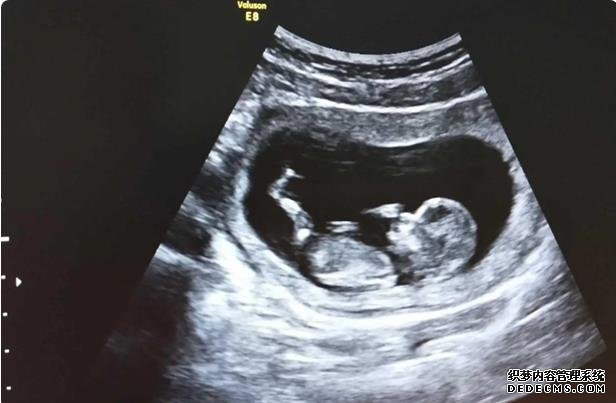

大多数的女性在选择做试管婴儿手术的时候,可能也都有自己的一些想法,比如他们在选择做试管婴儿手术的过程当中,可能更倾向于第三代试管婴儿,那么苏州市立医院三代试管究竟有此哪一些认知?其实很多人可能在这方面对试管婴儿的成功率认知并没有我们想象当中那么多,这种情况下我们要结合自己的实际情况来看一下现有的试管婴儿的情况。

当我们在选择做试管婴儿手术的时候,尤其是第三代试管婴儿手术,大多数的人都会发现吃软的手术全部都是在麻醉医生的麻醉状态下进行的,手术过程相对较短,而且整个手术都是无痛,安全性能相对较高,手术之后几分钟之内就可以完全清醒,所以说试管婴儿胚胎移植的手术不需要麻醉,手术之后平躺半个小时就可以。